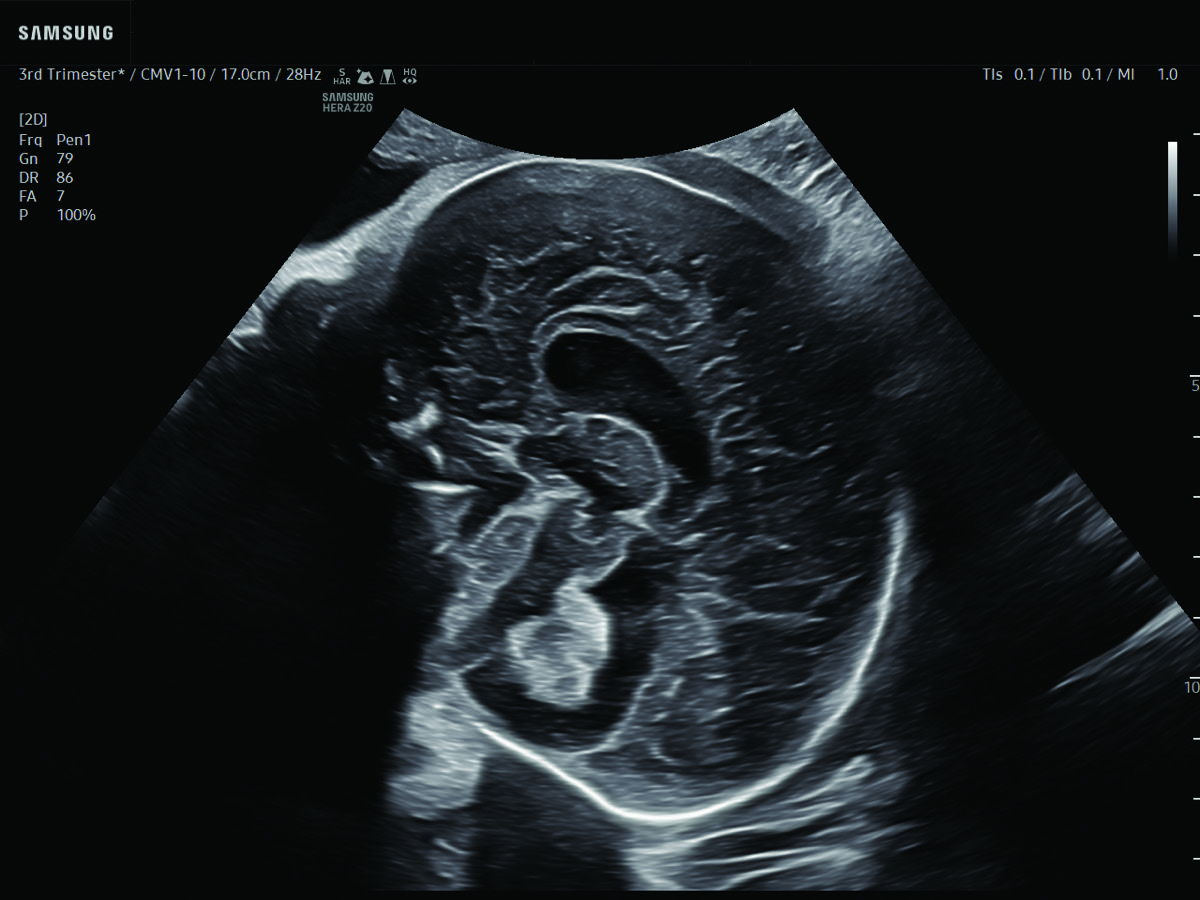

Comprehensive, advanced and expert MFM care for high-risk pregnancies

- Fetal anomalies